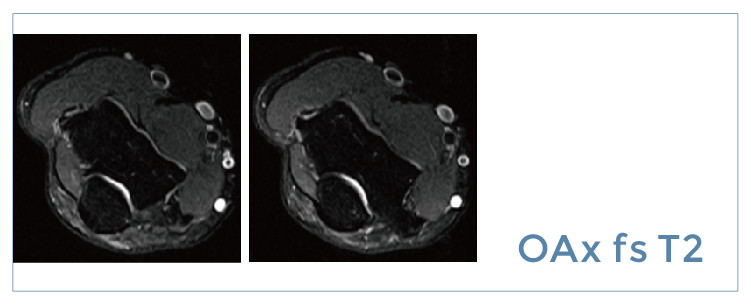

【朗润影像档案】20190726磁共振影像病例结果讨论